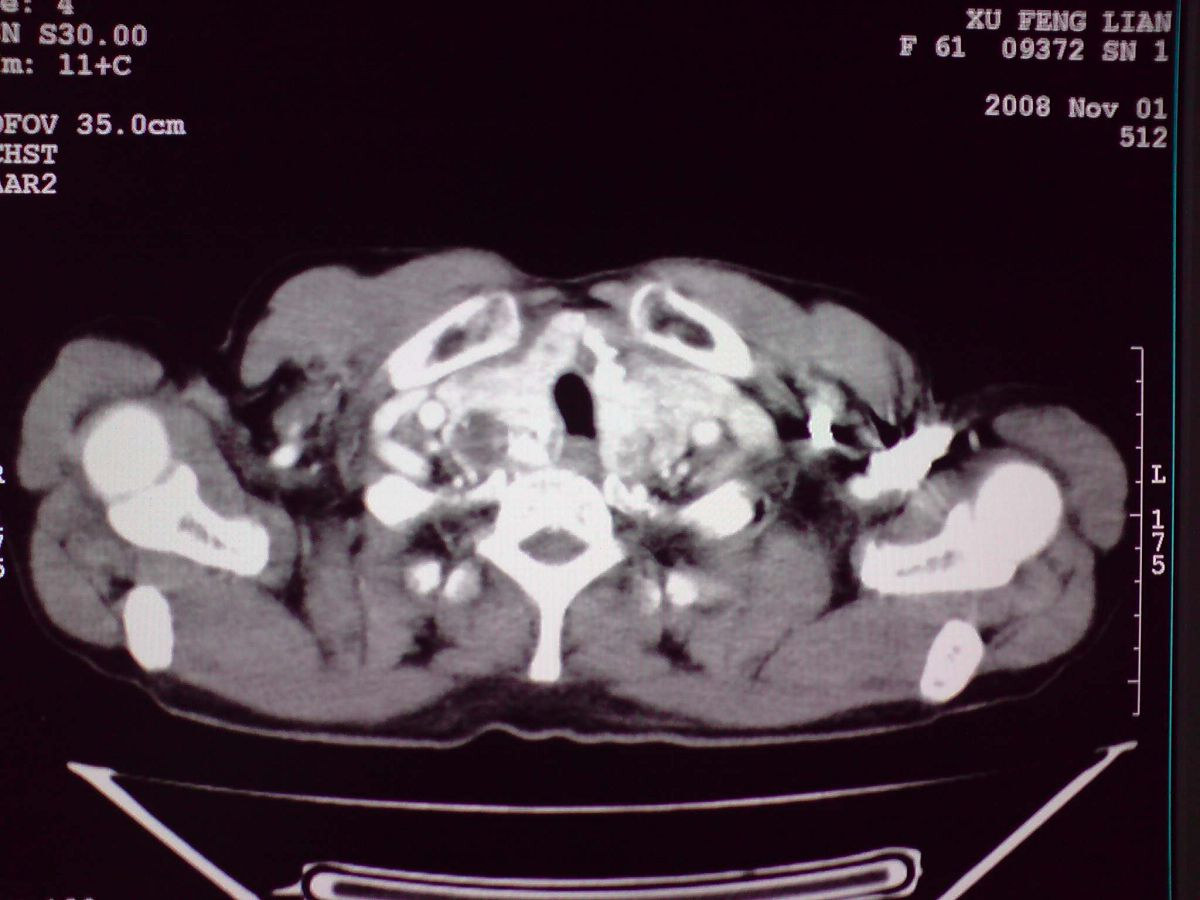

患者女性,65岁,无明显不适,甲状腺功能无异常

双侧甲状腺肿大,向下部分突入胸腔,双侧甲状腺内密度不均,可见结节状低密度影,并见散在斑点状钙化,增强后病灶实性部分强化明显,气管受压稍变窄左移。

考虑:双侧甲状腺腺瘤可能,不除外甲状腺癌。

胸内甲状腺,双侧结节状甲状腺肿伴右侧甲状腺腺瘤。

甲状腺左右叶增大,并向下突入胸腔内,其内可见多发条片状钙化影及囊性低密度影,邻近组织及血管无浸润、包埋征像,双侧结节性甲状腺肿伴右侧甲状腺腺瘤形成可能性大,甲状腺癌待排;因病人就要手术,期待结果。